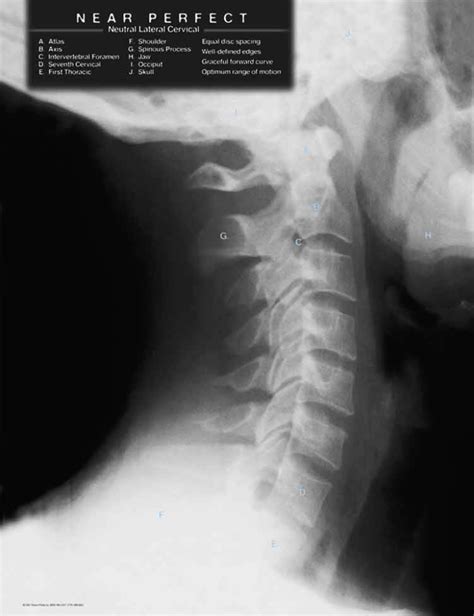

Diagnosis usually starts with a physical examination by a healthcare professional. They’ll ask about how the injury happened and the symptoms you’re experiencing. They’ll also check your range of motion and look for any areas of tenderness. Imaging tests, like X-rays, might be used to rule out any other injuries, like fractures, but they typically don’t show soft tissue injuries like sprains and strains directly. More detailed imaging, such as an MRI, could be used if the healthcare provider suspects a more severe injury. During the physical exam, the doctor might perform specific tests to assess the function of your spine and rule out other potential causes of pain.